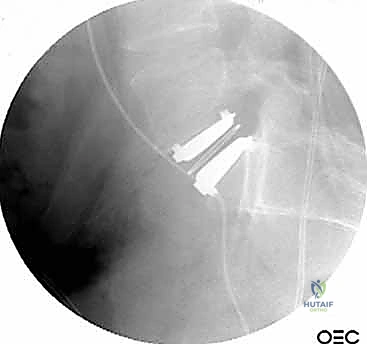

الخطوة 5: التثبيت (Fixation)

لضمان أقصى درجات الثبات والسماح للعظم بالاندماج بمرور الوقت، يتم تثبيت القفص باستخدام شريحة معدنية صغيرة ومسامير من التيتانيوم تُثبت في الأجسام الفقرية من الأمام. في بعض الحالات، قد يرى الدكتور هطيف ضرورة إضافة تثبيت خلفي بمسامير عبر الجلد (Percutaneous Pedicle Screws) لزيادة الدعم.